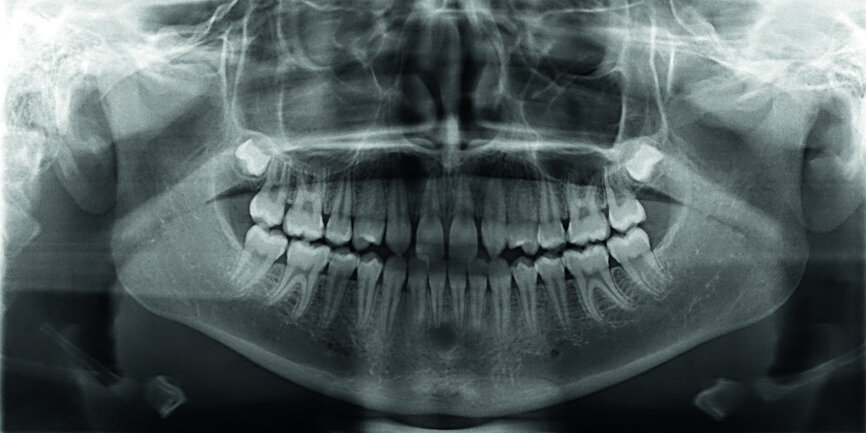

Then occlusal analysis (Figs. 11–21) was performed:

- Skeletal Class III (Fig. 17).

- Dental Class I.

- Maxillary hypoplasia with lower arch dental compensations.

- Insuficient overbite and overjet.

- Upper spacing due to the laterals agenesis (Fig. 18).

- Upper midline deviated to the right.

- Initial CR mounting (Figs. 19–21).

Finally space analysis was carried out (Tables 1a & b).

It was concluded that maxillary hypoplasia was an indication for space opening. Considering the young age of the patient, the skeletal pattern and the high demands regarding aesthetics, it was decided to:

- Open spaces for two implants, but in the posterior area: 14 and 24.